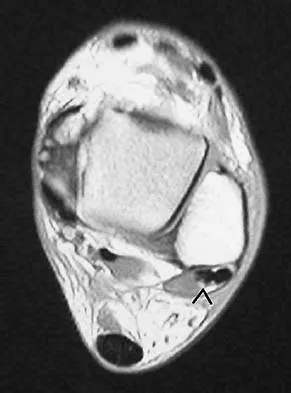

Question 318High Yield

A 57-year-old woman with diabetes mellitus has purulent drainage from a lateral incision after undergoing open reduction and internal fixation of a displaced ankle fracture 10 days ago. Examination reveals moderate erythema and a foul odor coming from the wound. Cultures are obtained. What is the next most appropriate step in management?

Explanation

Early postoperative wound infections after open reduction and internal fixation should be treated with aggressive debridement and maintenance of stability of the fracture. If infection persists following healing of the fracture, the hardware should be removed. Carragee EJ, Csongradi JJ, Bleck EE: Early complications in the operative treatment of ankle fractures: Influence of delay before operation. J Bone Joint Surg Br 1991;73:79-82.